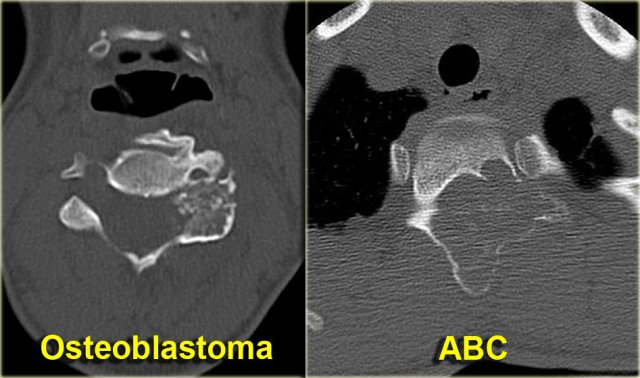

Osteoblastoma

Osteoblastoma is a rare solitary, benign tumor that produces osteoid and bone.

Consider osteoblastoma when ABC is in the differential diagnosis of a spine lesion (figure).

A typical osteoblastoma is larger than 2 cm, otherwise it completely resembles osteoid osteoma.

Discriminator:

- Mention when ABC is mentioned.

Aneurysmal Bone Cyst

ABC is a solitary expansile well-defined osteolytic bone lesion, that is filled with blood.

It is named aneurysmal because it is expansile.

ABC is thought to be the result of a reactive process secondary to trauma or increased venous pressure.

Sometimes an underlying lesion like GCT, osteoblastoma or chondroblastoma can be found.

ABC can occur almost anywhere in the skeleton.

Discriminators:

- Must be under age 30.

- Must be expansile